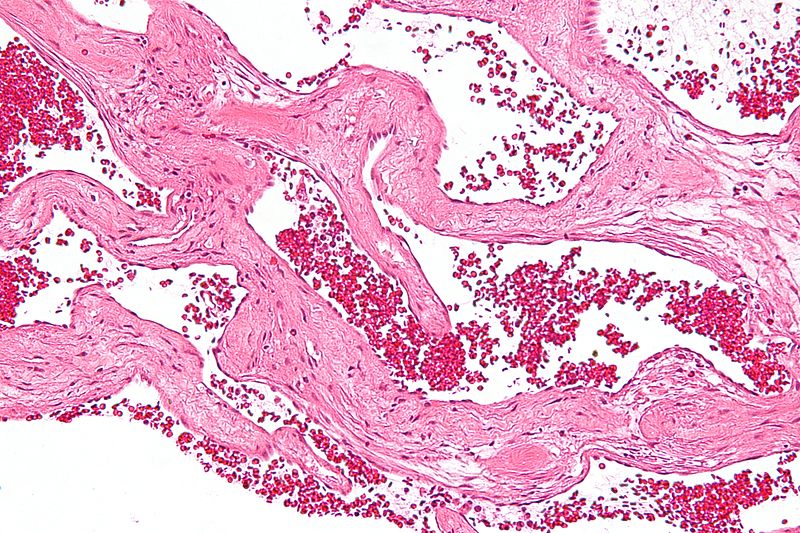

간혈관종은 간에 발생하는 가장 일반적인 양성종양으로 성인의 3~4% 정도에서 인정됩니다. 미세한 혈관이 모인 종양으로 타고난 체질이라고 알려져 있지만 자세한 원인은 알 수 없습니다.